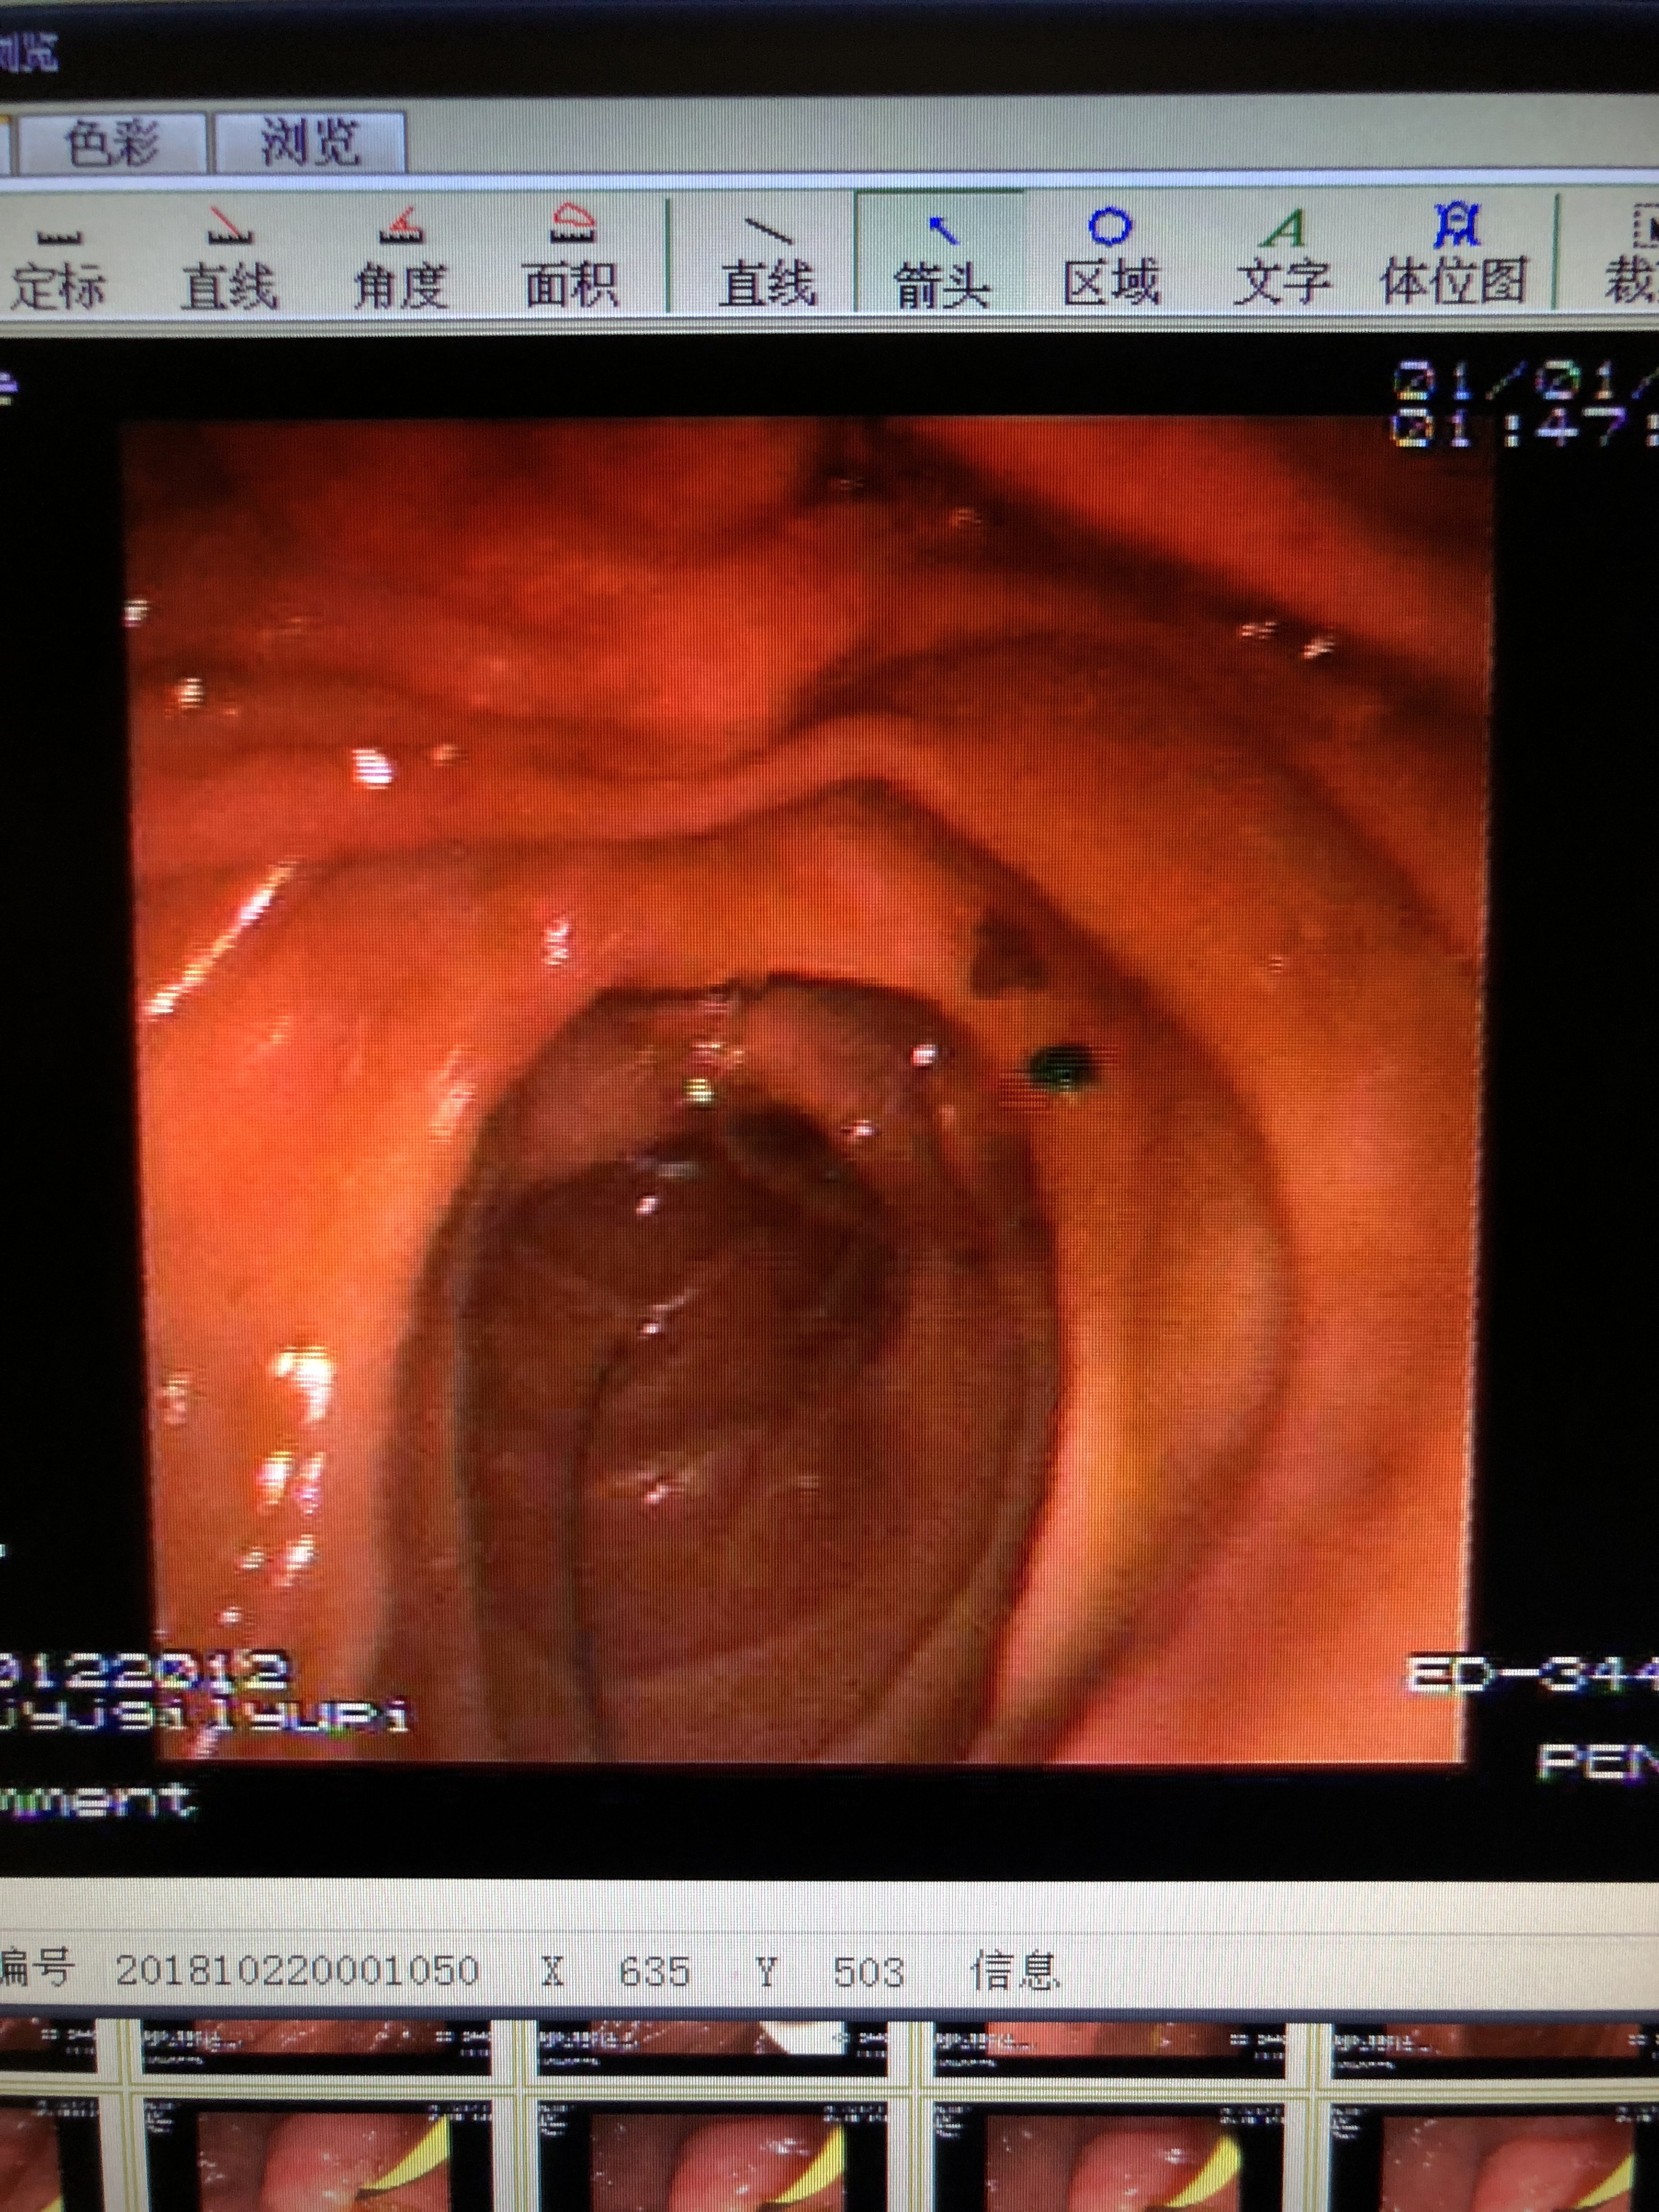

胆管下端狭窄即缩窄性乳头炎伴胆管扩张并

3024x4032 - 1480KB - JPEG

3024x4032 - 2693KB - JPEG

3024x4032 - 2433KB - JPEG